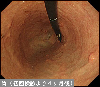

A case of multiple metastatic lesions in the stomach and large intestine from the breast cancer.

Endoscopy